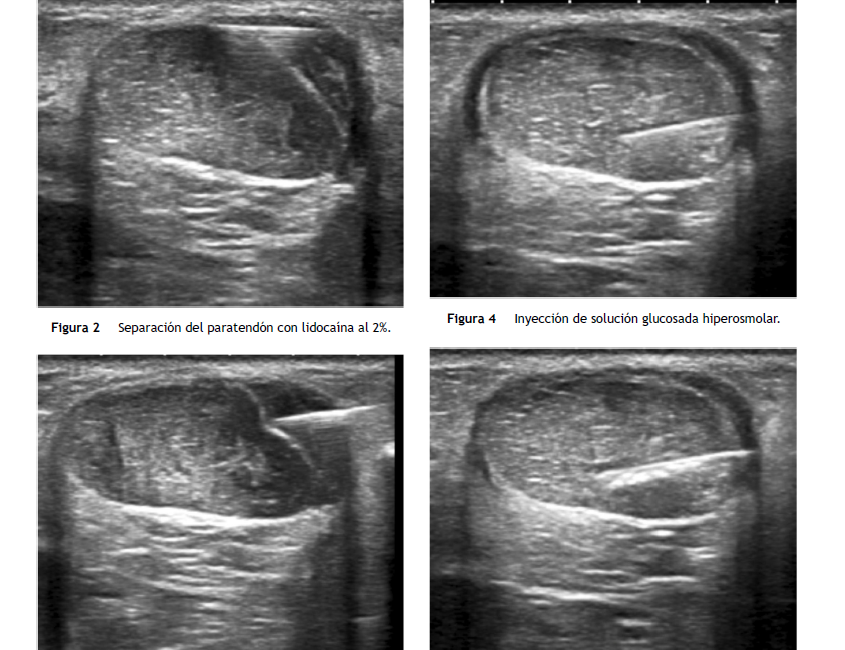

Patología muy frecuente, especialmente en las personas que practican deportes como el fútbol, baloncesto, atletismo, tenis, pádel... ytambién en personas con sobrepeso y/o tienen un trabajo con muchas horas de pie Eficacia de la proloterapia con glucosa hiperosmolar intratendinosa en el tendón de Aquiles guiada por ecografía Es una técnica...